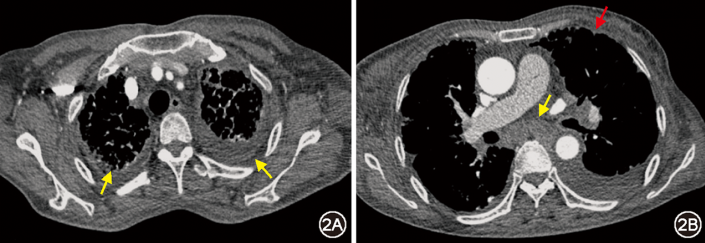

图1  治疗前(2024年9月10日)胸部CT:双肺弥漫网格(图1B红箭头)、磨玻璃影(图1B黄箭头),小叶间隔增厚(图1A箭头),支气管血管束增粗(图1C箭头)

本例患者影像表现为支气管血管束增粗、小叶间隔增厚、磨玻璃及网格影,呈“淋巴道分布模式”,伴纵隔淋巴结肿大、胸膜增厚及胸腔积液。在接诊“淋巴道分布模式”的肺间质病变患者时,应鉴别癌性淋巴管炎、结核感染、结节病等疾病。患者虽为老年女性,有右乳肿大,但病情发展相对缓慢,影像提示淋巴水肿,故除外癌性淋巴管炎。患者T-SPOT.TB阳性,纵隔淋巴结病理见炭末沉积,伴多核巨细胞,在难以明确诊断时,接受诊断性抗结核治疗,然而效差,除外结核感染。患者影像也符合结节病表现,且血ACE升高,对结节病有一定提示意义,但结节病中ACE阳性率不足50%,其他疾病如肺结核也可升高,故其阳性不能作为结节病诊断标准[1, 2];此外,患者伴顽固性胸腔积液,在结节病中少见[3];BALF淋巴细胞占比低,激素治疗无效,排除结节病诊断。此外,尘肺病及肺淋巴管疾病亦有类似表现,应予鉴别。